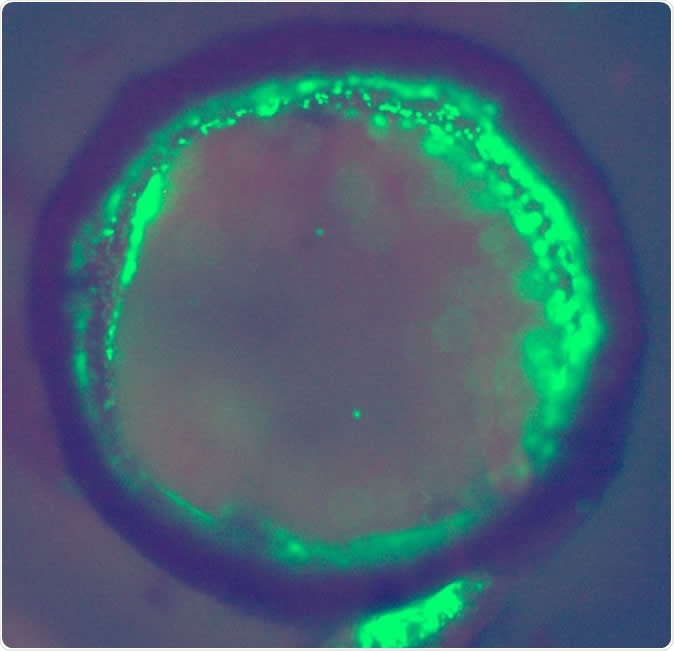

Cross-section of a bioprinted tubular structure with endothelial cells (green) on and embedded within the wall. Image credit: Professor Alvaro Mata